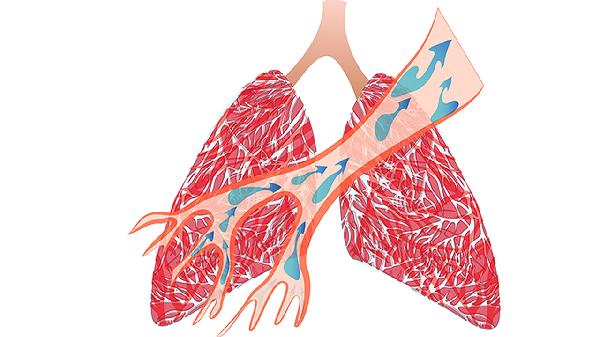

密闭空间二氧化碳浓度升高,影响肺部气体交换。建议留5-10厘米窗缝,使用空气净化器更好。